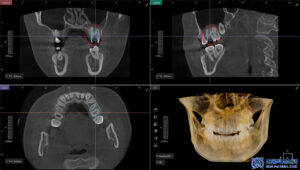

사랑니는 개인에 따라 매복 상태나

신경과의 위치가 달라

정밀한 진단이 중요하기 때문에,

3D CT를 촬영하여 사랑니의 위치와 형태,

주변 신경과의 거리 등을

정밀하게 확인했습니다.

이를 바탕으로 발치 과정에서

발생할 수 있는 위험 요소를

사전에 파악하고,

보다 안정적인 사랑니 발치를

계획하였습니다.